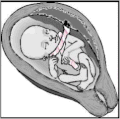

| Baby in the uterus with umbilical cord wrapped around its neck and arm | |

A nuchal cord is when the umbilical cord becomes wrapped around the fetus's neck.[1] Symptoms present in the baby shortly after birth from a prior nuchal cord may include duskiness of face, facial petechia, and bleeding in the whites of the eye.[1] Complications can include meconium, respiratory distress, anemia, and stillbirth.[1] Multiple wraps are associated with greater risk.[3]